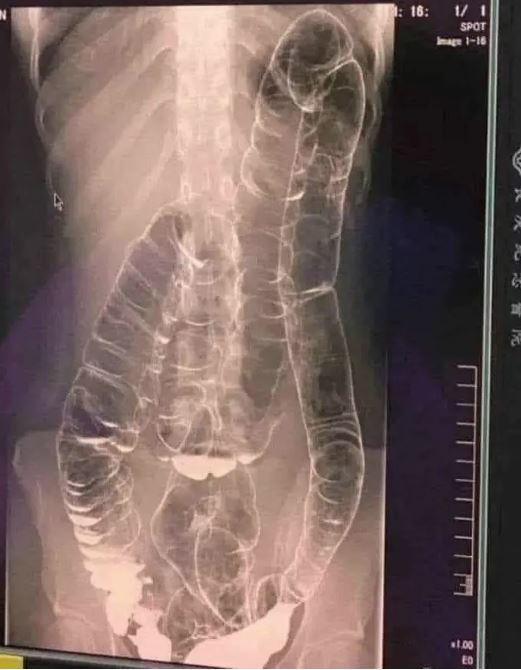

Chronic constipation is a common yet often overlooked condition. In extreme cases, prolonged constipation can lead to toxic megacolon, a life-threatening complication where the colon expands beyond its natural capacity, reaching the chest area and compressing vital organs like the heart.

When the colon is unable to expel waste properly, fecal matter accumulates, causing extreme bloating and distension. Over time, the colon loses its natural folds and ability to contract, resulting in: